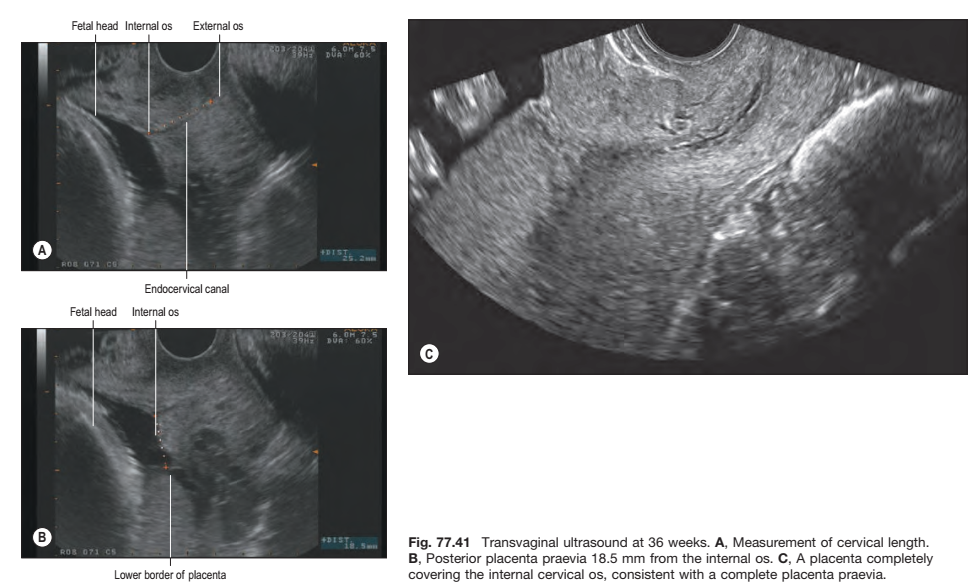

Fig. 77.41 Transvaginal ultrasound at 36 weeks. A, Measurement of cervical length. B, Posterior placenta praevia 18.5 mm from the internal os. C, A placenta completely covering the internal cervical os, consistent with a complete placenta praevia.

Transvaginal ultrasound examination allows for a robust evaluation of the cervix during pregnancy. Cervical length, dilation of the internal os and bulging of the membranes into the canal can all be assessed

(Fig. 77.41). Detection of a shortened cervical length in mid-gestation using transvaginal ultrasound is a strong risk factor for premature delivery and has been used clinically to identify women at high risk of preterm delivery in order to plan appropriate management (Fonseca et al 2007, Hassan et al 2011, Owen et al 2009). Emerging sonographic and MRI technologies are being used to investigate both the biomechanical properties and the microstructure of the cervix in pregnancy and promise to shed light on the poorly understood mechanisms involved in both normal and pathological cervical shortening in human pregnancy (Feltovich et al 2012, House et al 2013).

In about 1% of pregnancies, the position of the placenta will remain over, or in close proximity to, the internal cervical os at the end of pregnancy (see Fig. 77.41B; Fig. 77.42). This condition is called placenta praevia and can be associated with vaginal bleeding during pregnancy and labour. If the placenta covers the internal os, or the lower edge is less than 1–2 cm from the internal os, delivery by caesarean section is generally indicated.